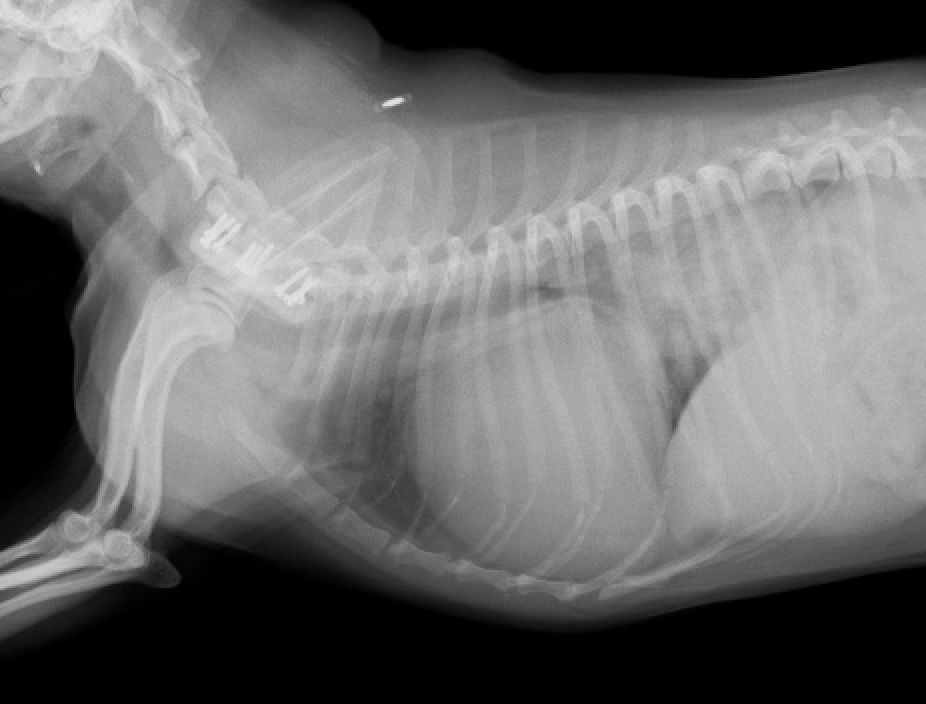

僧帽弁閉鎖不全症は、ステージが進行すると肺水腫というとても苦しい症状が出現する状態に陥ります。苦しさとしては溺れているように苦しいと表現されるほど、辛い症状となってしまいます。また肺水腫が出現するとstageはC以上と判定され、場合によっては最も重度なstageDと評価される場合もあります。stageC以上のわんちゃんは、残念ながら長生きできず、ある論文による研究では270日前後(1年以内)で亡くなってしまうということも言われております。

僧帽弁閉鎖不全では、弁の腱索という紐状の部分が断裂し、急激な悪化を示す場合が多く、肺水腫を呈している症例の大部分は腱索断裂を起こしております。また心臓は逆流により拡大しているため、弁と弁の間が拡張し広がっているため、弁が接合する面積が減少しておりより逆流しやすい状況となっています。

心臓の手術がうまく行くと、僧帽弁逆流はほとんどなくなり、心拡大は良化し苦しかった肺水腫の症状は消失します。逆流がほとんどなくなった場合にはこれまで飲んでいた沢山の薬は必要なくなる場合が多いです。(100%ではございません。)